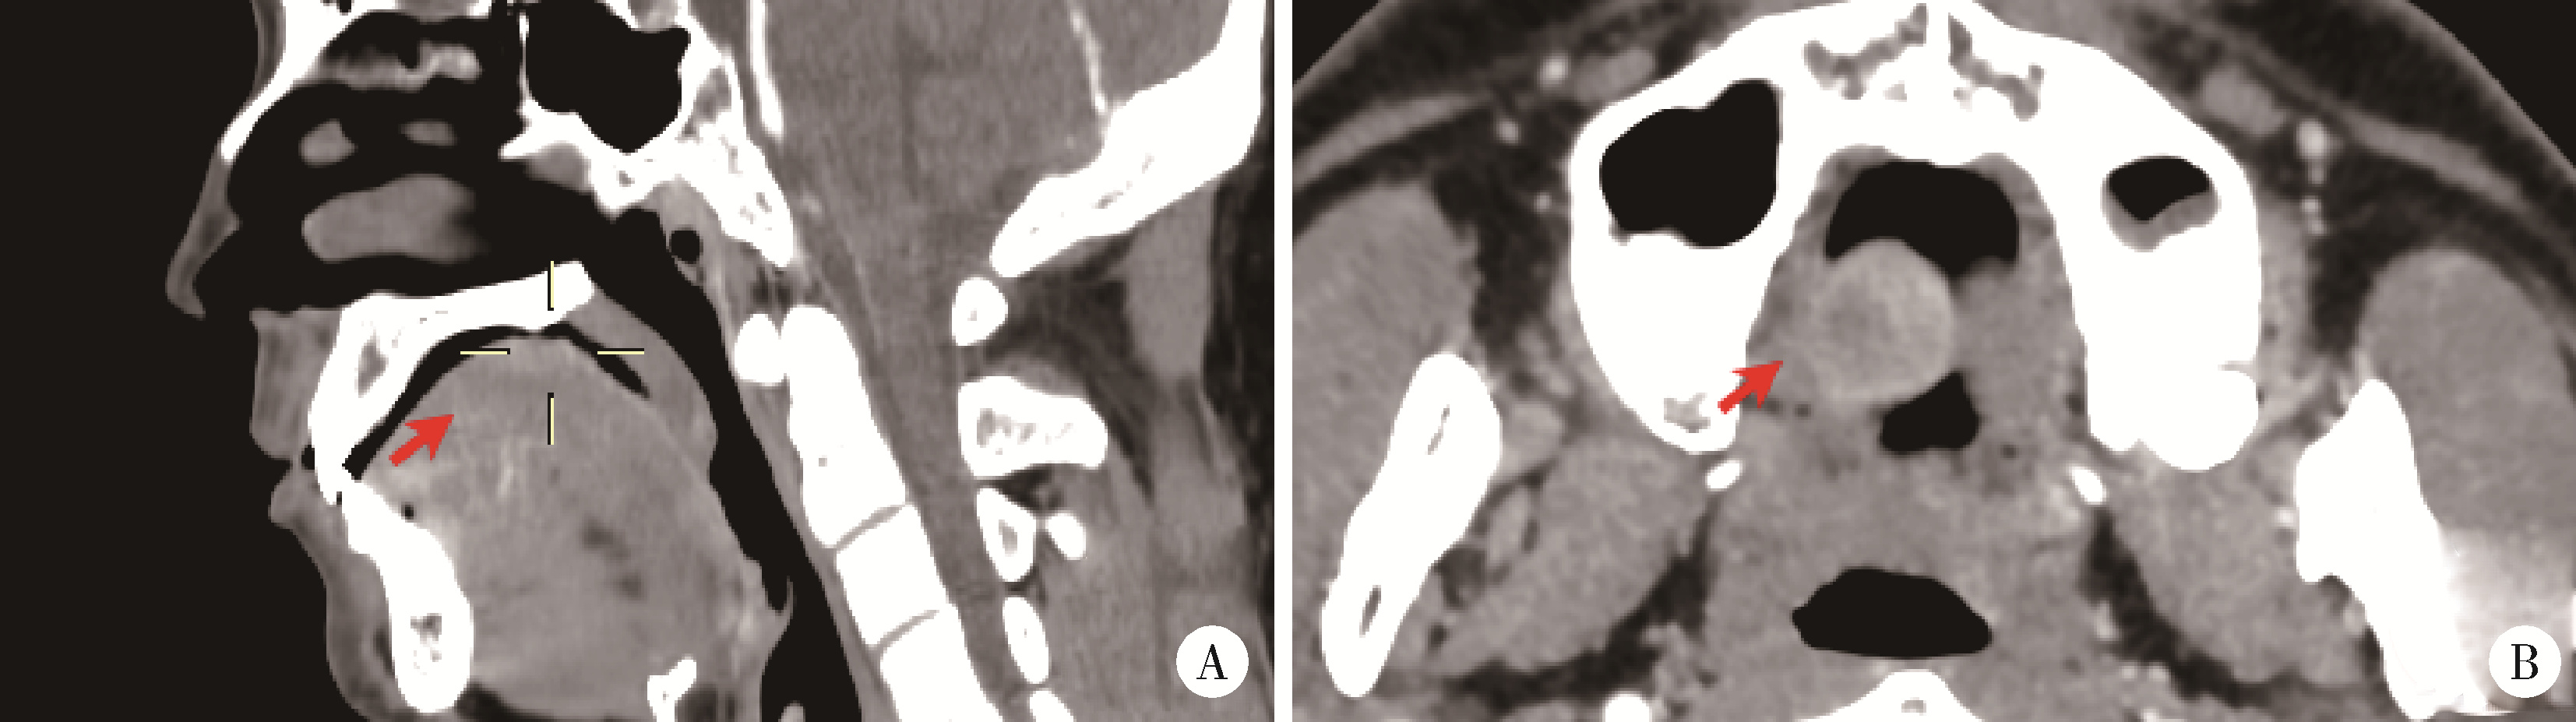

Figure 2

Case 1, CT showed a mildly enhanced round soft tissue mass on the dorsum of the tongue(arrowhead)"